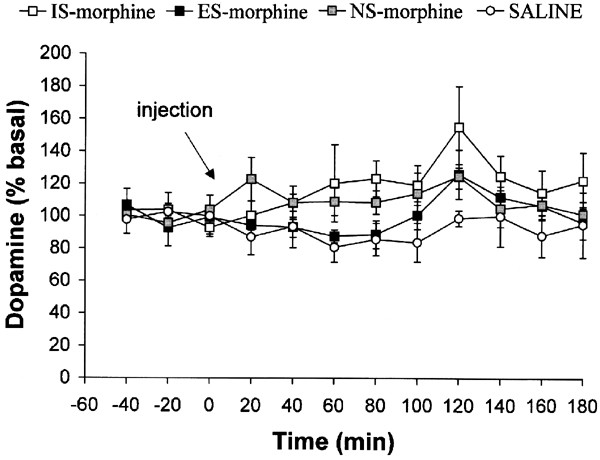

There was no significant Group difference in DA efflux between saline-treated rats after prior IS, ES, or NS, F(2,4)=228, _p_=0.81, and no Group × Time interaction, F(22,44)=1.24, _p_=0.27, so the data from these groups were pooled and labeled SAL. There was no significant group difference in DA efflux (Figure 5), F(3,25)=2.85, _p_>0.05. There was a significant main effect of Time, F(11,275)=2.14, p<0.05. _Post hoc_ tests indicated that this reflected an increase in DA at 120 min compared to basal levels. There was no significant Group × Time interaction, F(33,275)=0.90, _p_>0.05. There were no significant effects of Hemisphere on DA efflux (data not shown).

Figure 5

DA efflux (expressed as a percentage of baseline) in the mPFC during a morphine (3 mg/kg) or saline challenge (indicated by the arrow) 24 h after exposure to IS, ES, or NS. Neither exposure to IS nor morphine affected morphine-induced DA efflux in the mPFC. Data are means±SEM for six to eight rats.